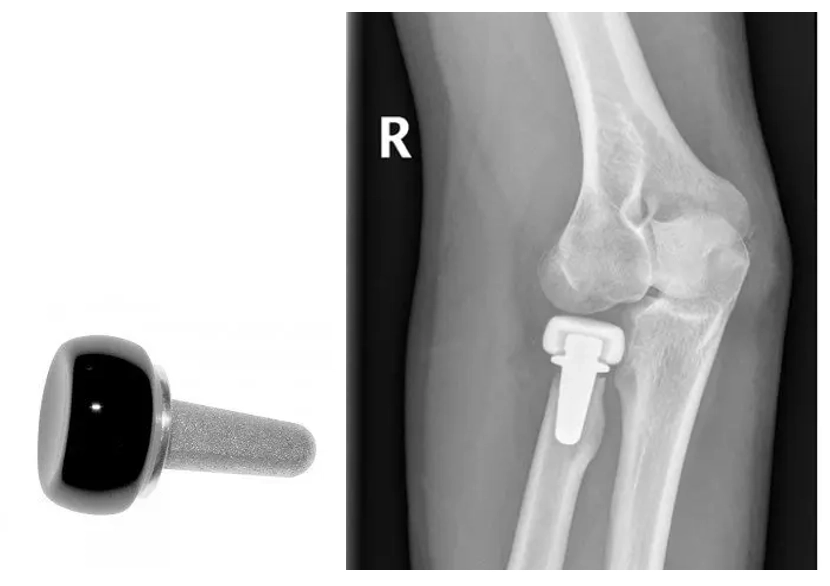

Elbow Replacement

Radial Head Replacement